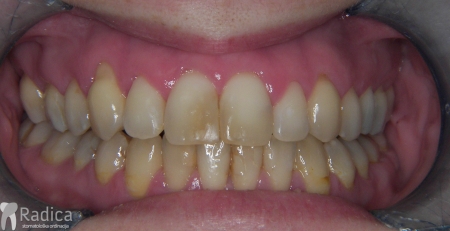

Slučaj 5: ispravljanje kompresije i križnog zagriza Invisalign full terapijom